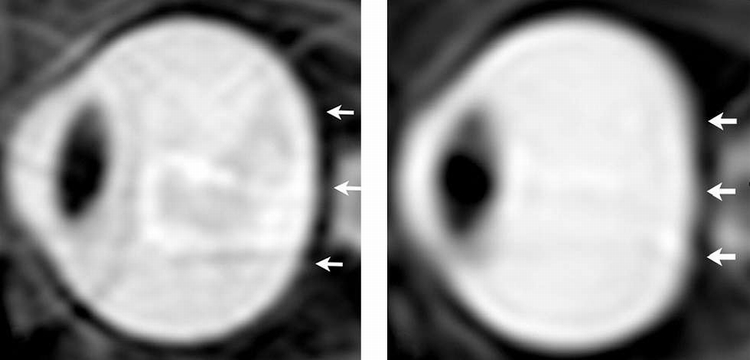

一张太空人眼睛的之前和之后MRI照片。

研究小组从7次长期任务和9次短期任务的太空人的眼部,进行任务前和任务后的高解析度MRI扫描。

相较于短时间任务的太空人,长时间任务的太空人眼睛的平坦度增加,而且眼球后方有较高含量的CSF。分析也显示,CSF含量越高,观察到的变形就越大。

这个眼睛变平而且视觉神经被CSF弯曲。